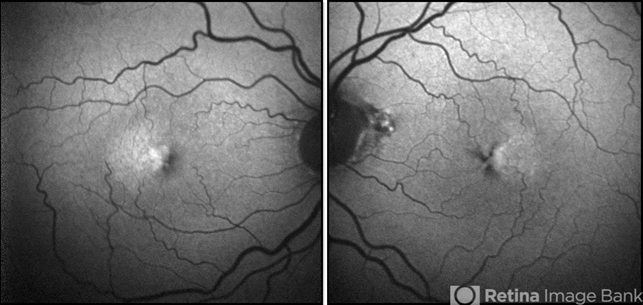

- Mac Tel type 2, retina

- Fundus autofluorescence photograph of both eyes of a patient with MacTel type 2. Fundus autofluorescence can aid in early diagnosis of disease, showing development of foveal hyperautofluorescence corresponding to deterioration of macular pigment and possible damage to Muller cells. As the disease progresses, RPE hyperplasia may develop and manifests as hypoautofluorescent regions.